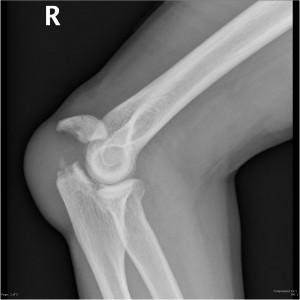

- Рентгенография поврежденного сустава и кости, выполненная в нескольких проекциях.

- В некоторых случаях, если результаты рентгенографии сложно интерпретировать, может быть назначено обследование с помощью КТ или МРТ.